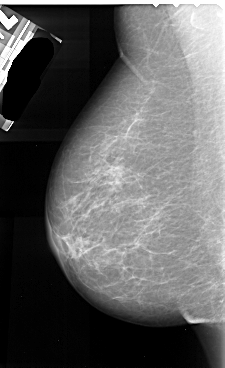

A_1040_1.LEFT_MLO

LEFT_MLO LINES 5506 PIXELS_PER_LINE 3361 BITS_PER_PIXEL 16 RESOLUTION 42 NON_OVERLAY